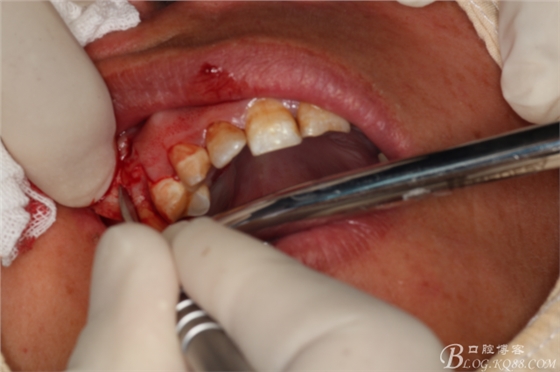

圖8.翻瓣

圖9.暴露出16根尖上方的囊壁